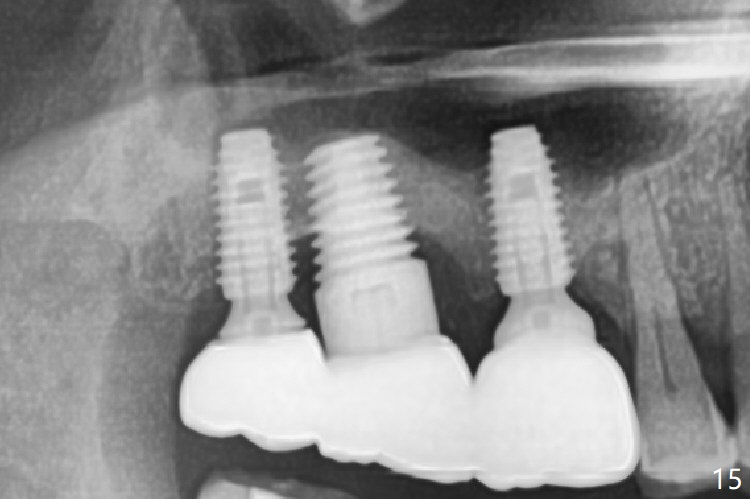

Periimplantitis develops with bone loss 4 years 5 months post cementation (Fig.15). It appears that the implant should be removed (Fig.16, unipost cemented with Ketac, prepare special screw driver after handpiece making a slot), followed by bone graft (Fig.17 red circles), particularly mesial to #1 implant and PRF. Prepare Titanium brush to clean the exposed implant threads of #1 implant. When the defect heals (with increased bone height, Fig.18 greyish area), place a smaller implant (green) with guide.